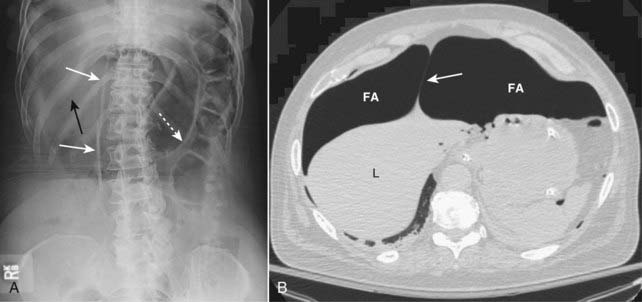

image

Figure 15-9 Falciform ligament sign.

A, Free intraperitoneal air may surround the normally invisible falciform ligament on the anterior edge of the liver causing that thin, soft tissue structure to become visible (solid white arrows) just to the right of the upper lumbar spine. Notice also that both sides of the stomach wall are visible (Rigler sign) (dotted white arrow) and there is increased lucency in the right upper quadrant (solid black arrow) in this patient with a large pneumoperitoneum from a perforated gastric ulcer. B, The falciform ligament (solid white arrow) is outlined by free air (FA) on either side of it, anterior to the liver (L).